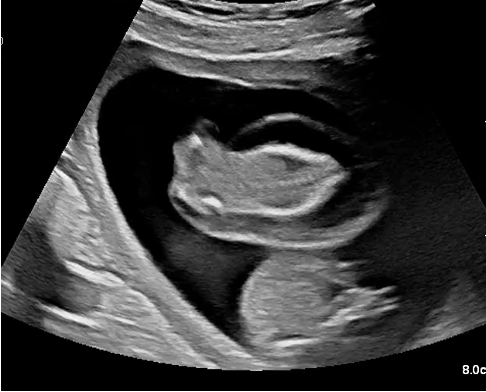

TRAP, feto acardio acefalo

La sequenza TRAP è una condizione rara, che si verifica in 1 su 100 gravidanze gemellari monocoriali ed in 1 su 35 000 gravidanze in totale. I gemelli monocoriali sono gemelli identici che condividono la stessa placenta, con anastomosi vascolari che connettono il circolo sanguigno dei due feti. La TRAP è una complicanza che si verifica in questo circolo condiviso quando uno dei due gemelli muore in una fase precoce della gravidanza.

Nella sequenza TRAP, il sangue del gemello sano scorre in direzione inversa verso il gemello deceduto. Questo gemello non ha più una propria attività cardiaca ed è pertanto definito “gemello acardico”. Il gemello sano pompa il sangue verso il gemello acardico, ed è pertanto definito “gemello pompa”. Grazie al flusso sanguigno proveniente dal gemello pompa, il gemello acardico continua a crescere. Questo flusso retrogrado, però, rappresenta uno stress eccessivo per il cuore del gemello pompa, che può andare incontro a scompenso cardiaco e aumentato output urinario. Conseguentemente, lo scompenso cardiaco può causare la morte del gemello pompa, e l’aumentata produzione di urina può determinare un accumulo di liquido amniotico con aumento del rischio di parto prematuro.